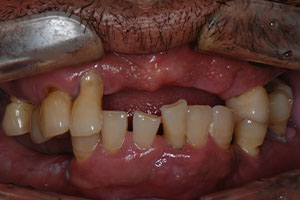

치료증례 전후사진

Before & After